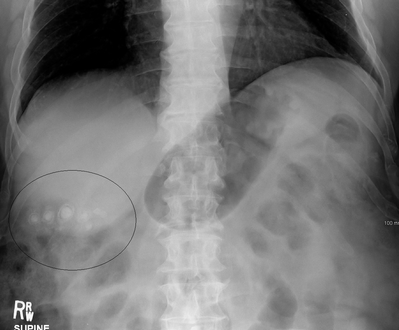

صور طبقية محوسبة لحصوات المرارة.

عادة ما يتأكد التشخيص عن طريق التصوير بالموجات الصوتية على البطن. تقنيات التصوير الأخرى المستخدمة هي ERCP وMRCP. قد يتم الكشف عن مضاعفات الحصوة في تحاليل الدم.[2]

في الموجات فوق الصوتية على البطن، عادةً ما يكون لحصوات المرارة الغارقة ظل صوتي خلفي. في حصوات المرارة العائمة، يُشاهد صدى الصدى (أو قطعة أثرية على شكل ذيل المذنب) بدلاً من ذلك في حالة سريرية تسمى الورم العضلي الغدي تكون هناك علامة أخرى هي ثالوث جدار الصدى والظل (WES) (أو الظل المزدوج القوس) والذي يعد أيضًا من سمات حصوات المرارة.[37]